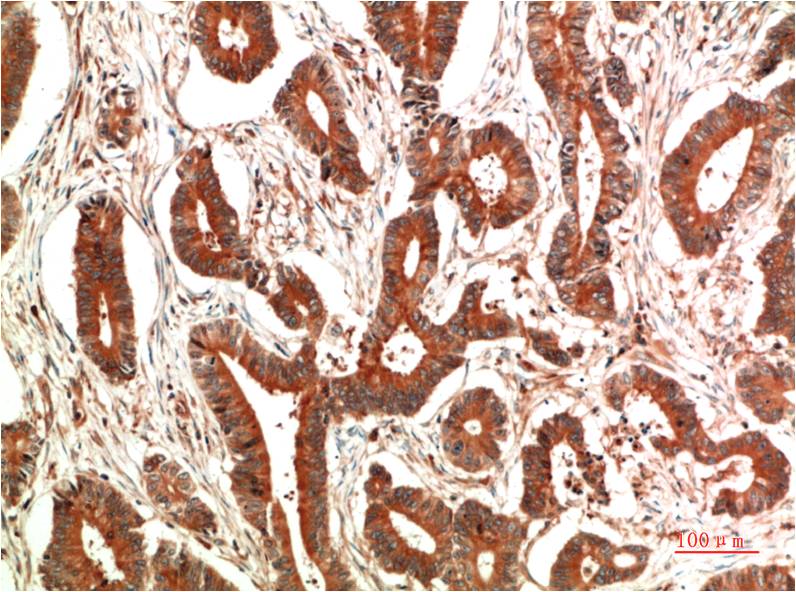

Immunohistochemical analysis of paraffin-embedded Human Colon Carcinoma Tissue using c-Jun(EM1338)Mouse mAb diluted at 1:200.

Immunohistochemical analysis of paraffin-embedded Human Ovarain Carcinoma Tissue using c-Jun(EM1338)Mouse mAb diluted at 1:200